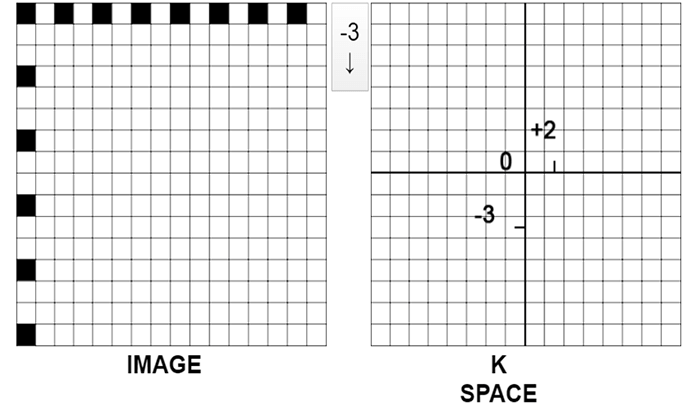

The K space is the frequential equivalent of the image which is a spatial representation. Example: We take one white square for which we decide to blacken every other box going toward the right and one out of 3 boxes going toward the bottom.

This process is repeated until We fill in the entire grid according to this rule. Consider the horizontal filling to be the phase and the vertical to be the frequency.

Dimensions of the K Space

The dimensions of the Fourier space and the image are the same. This means that the size of the field and the size of the matrix we set in the scanner parameters are in fact the size of the FOV and the matrix of the Fourier space. It is the acquisition matrix. In reality, the image is reworked before restitution or reconstruction. In general, the image restored is a 5122 image. The size of the matrix represents the number of pixels or the number of tiny squares inside the large square. On a 512 matrix, there will be 512 rows of pixels and 512 columns of pixels.

Pixels of the K Space

Each pixel of the Fourier space codes for all pixels of the image. In other words, in each of the pixels of the K space, we will have information on all the pixels of the image.

Pixels of the Image

Each pixel of the image has been coded by all the pixels of the K space. In other words, each of the pixels of the image has received information from the entire K space.

The symmetry of the K Space

Center and Periphery of the K Space

One of the most important properties of the Fourier space is that the center contains information on contrast and the periphery contains information on spatial resolution. This notion is indispensable for understanding the notion of effective TE and for understanding how filling the Fourier space differently can be used to create specific vascular sequences.

Contrast and Resolution

To summarize, the center of the K space codes for the contrast resolution. Whereas, the periphery of the K space codes for the spatial resolution.